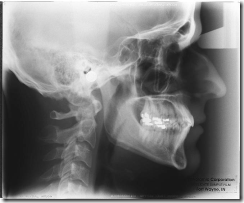

חדש במרפאה: מכונת צילום פנורמי דיגיטלי עם קרינה מינימלית.

- צילומים דיגיטליים 80% פחות קרינה מצילומים רגילים.

- 2010 CT’s and dental diagnosis

- 2009 CT scan interpretation course

- 2008 CT scan course